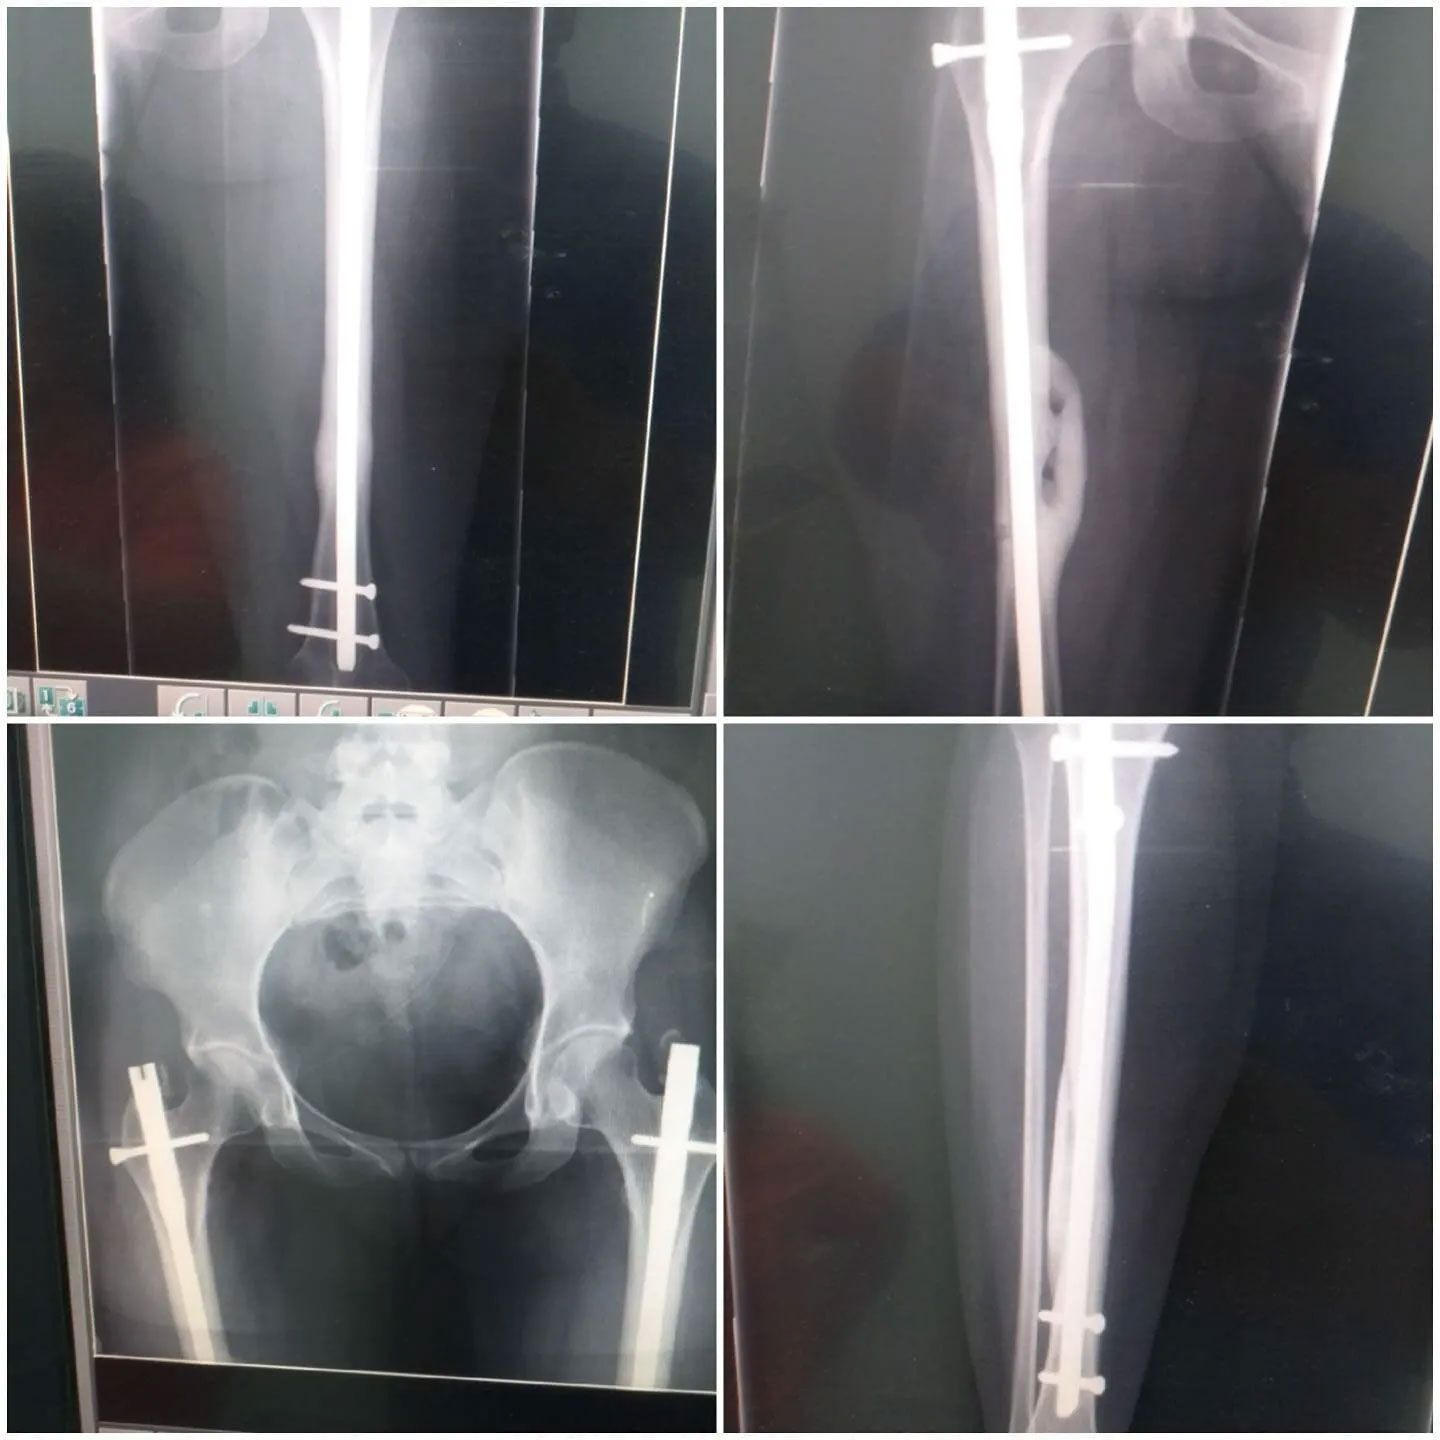

- Cirugía de fracturas

- Secuelas de fracturas